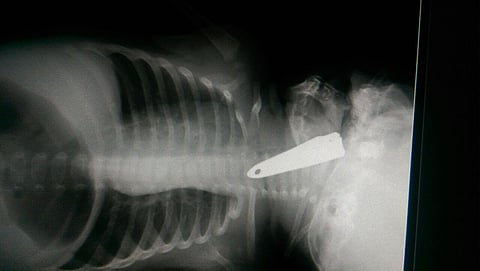

وأوضح المتحدث الرسمي بصحة المنطقة سعيد النقير، أنه بعد إجراء الفحوصات الطبية، اتضح أن الجسم الغريب عبارة عن قصاصة أظافر (مقراط)؛ حيث تم على الفور إدخال الطفلة إلى غرفة العمليات عن طريق فريق طبي متخصص مكون من استشاري جراحة الأنف والأذن والحنجرة الدكتور أحمد العتودي، وأخصائي الأنف والأذن والحنجرة الدكتور شاشي، واستشاري التخدير الدكتور حسن إسفنجة.

وتم بحمد الله استخراج الجسم الغريب، وإنقاذ حياتها واستقرار حالتها الصحية، وقد أشرف على نقل الطفلة مدير المستشفى المناوب فايز الأحمري.